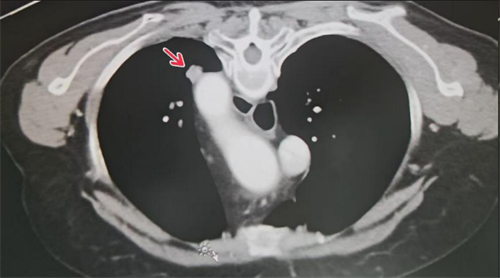

肺转移瘤邻近大血管

术中精准定位肺转移瘤位置